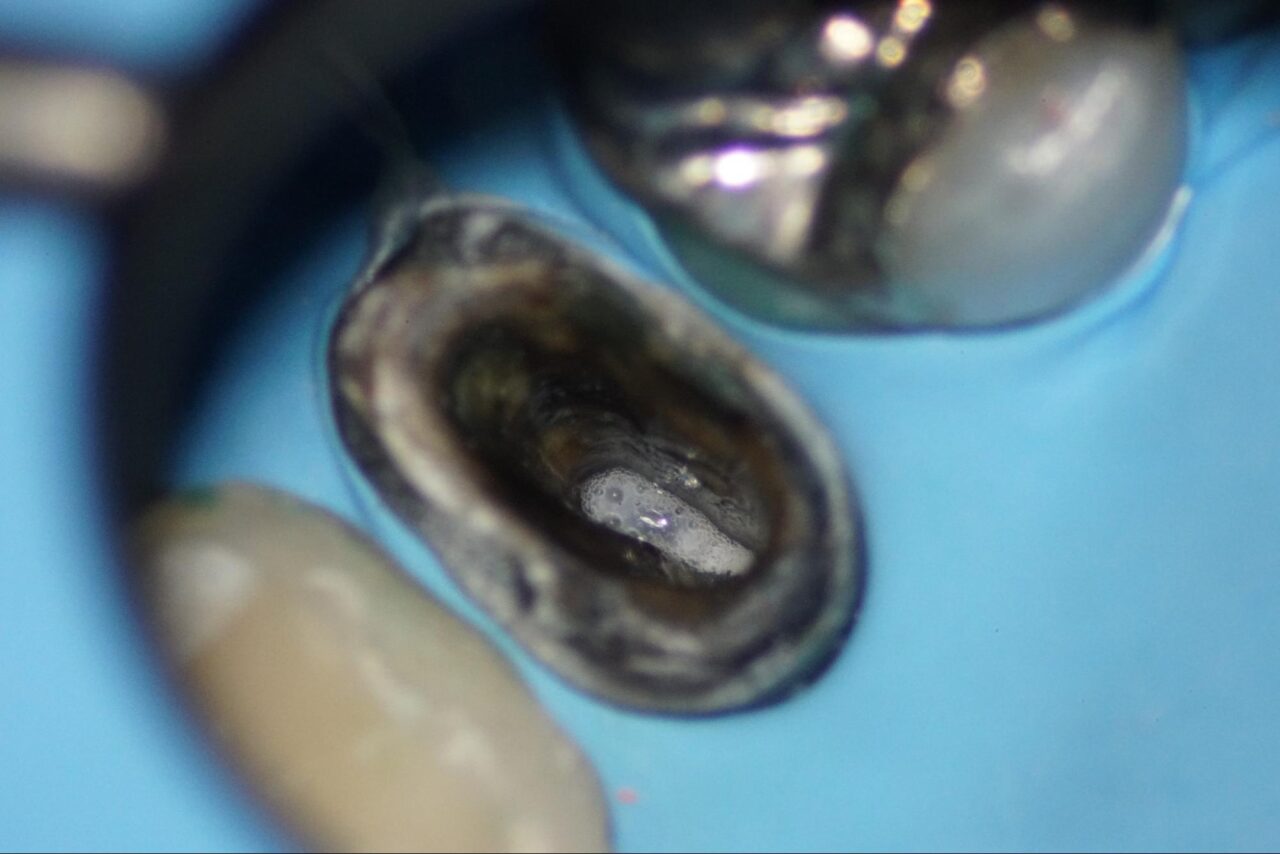

根管内を乾燥させるとクラックラインが確認できます。

標準的な診断基準であればこの時点で根管治療は終了になり、抜歯になります。

しかし吉松歯科医院では、私の過去の経験から接着して歯を残す事を行っています。

なぜ破れたのか?の原因除去を行わなければ、また短期間で破れてしまいます。

最終的なレーザー洗浄を行い、根管充填を行いました。